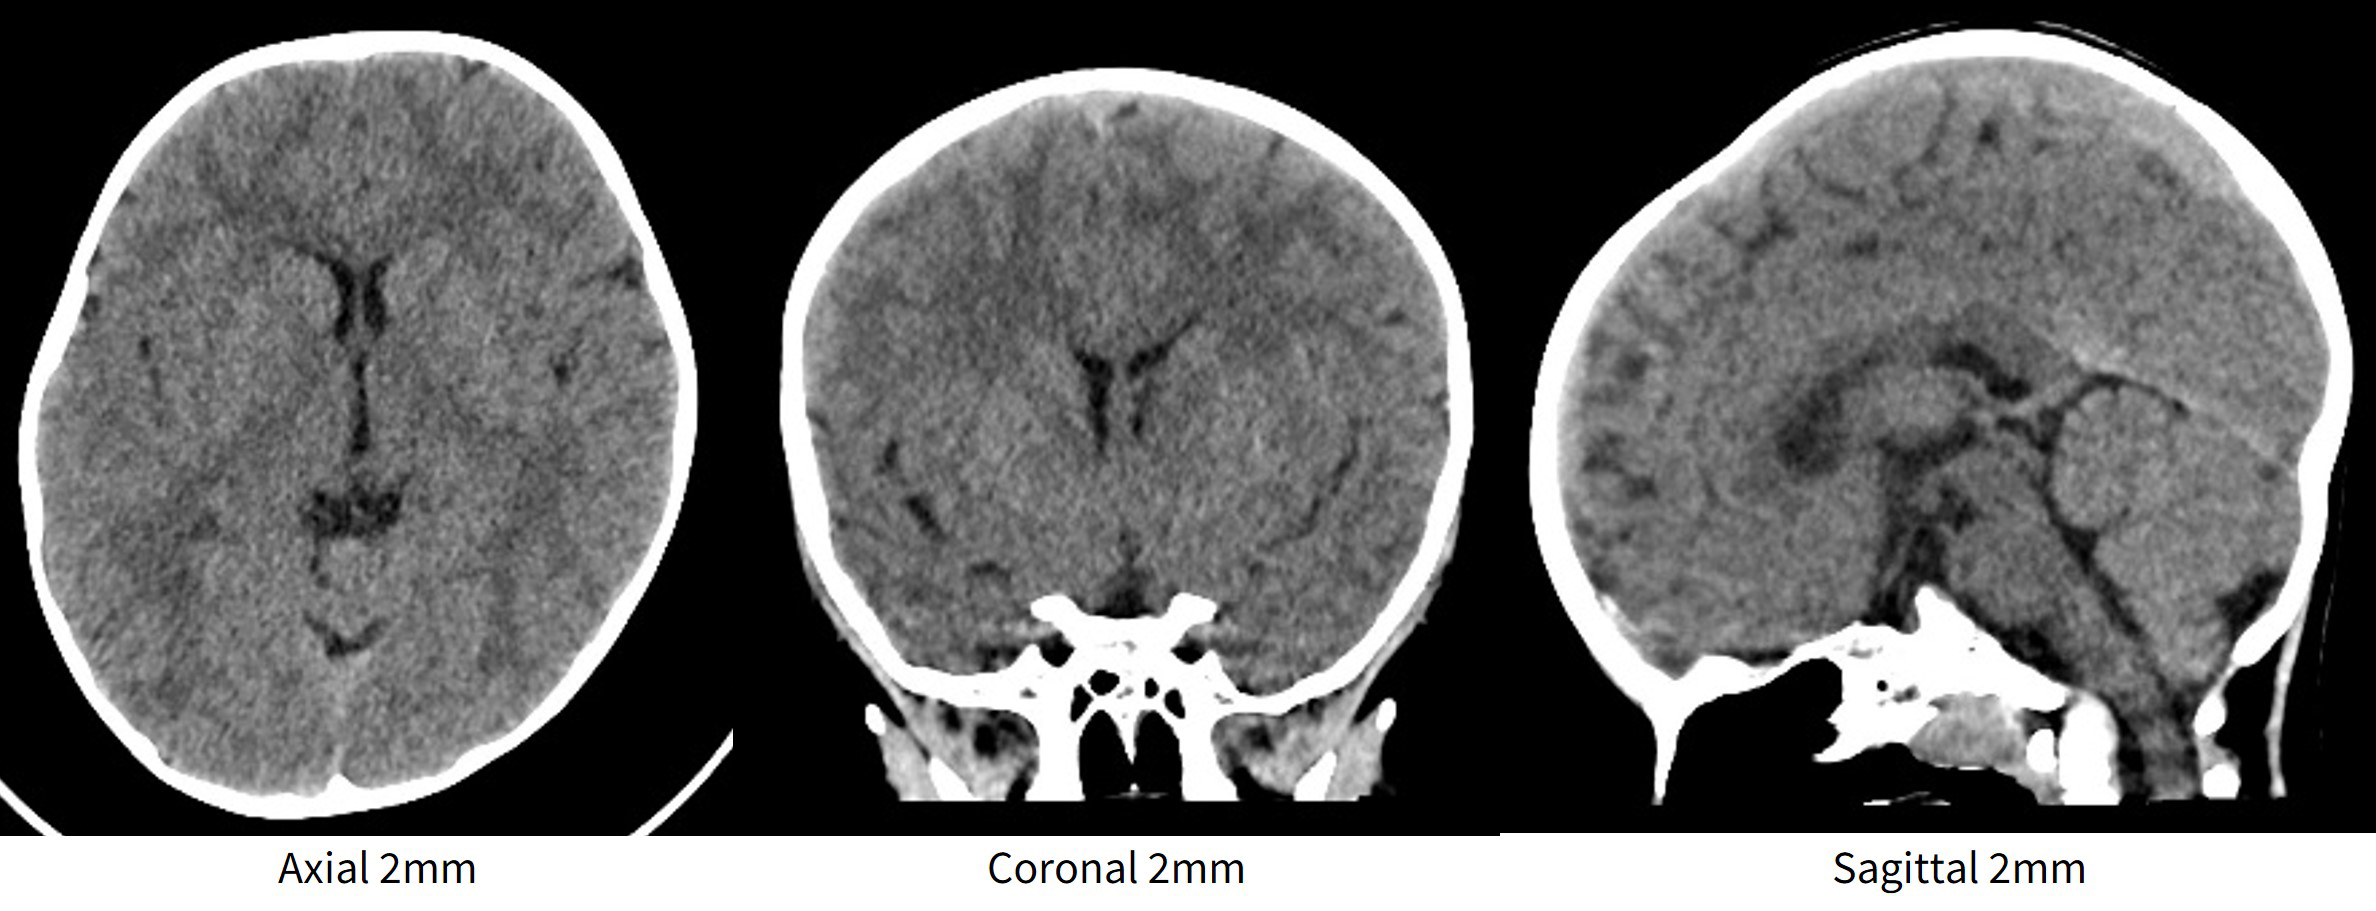

図1 2歳男児(撮影条件:ビーム幅160mmボリュームスキャン、120kVp、0.28sec/rot、NI3.0@5mm Stnd ODM、CTDIvol 27.64mGy)

ここで上記ワイドボリュームスキャンの最速条件にて撮影し再構成した画像を下に示す(図1)。症例は2歳男児、痙攣精査目的であり薬物鎮静無しでの検査であった。ベルトなどを用い体動抑制を行っていたが、体動の無い一瞬を狙って撮影する必要があった。見ての通り、最速条件であっても診断を妨げるアーチファクトも無く皮髄コントラストも明瞭に観察できるため、体動の可能性がある場合には積極的にワイドボリュームスキャンを使用している。これは焦点指向型3Dコリメータ、MMAR(Multi Material Artifact Reduction)、VHD(Volume High Definition Recon)などハードウェアとソフトウエア双方の優れた技術により成せる画質であると考える。